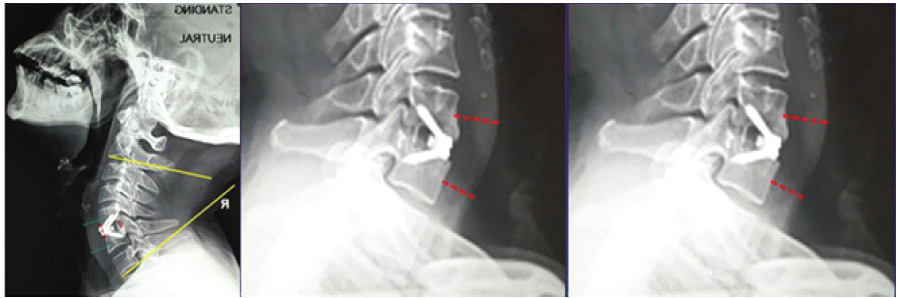

In addition to tracking operative time, intraoperative blood loss (BL), and length of hospital stay, radiological evaluations were conducted pre-operatively, post-operatively, and during follow-ups at roughly 3, 6, and 12 months. These assessments included cervical anteroposterior and lateral X-rays as well as computed tomography (CT) scans of the cervical spine [10]. The cervical Cobb angle was determined by measuring the acute angle formed between lines drawn along the inferior endplates of the C2 and C7 vertebral bodies on a lateral X-ray. The fused segment disc height (FSDH) was calculated as the average of the anterior and posterior disc heights, measured from the lower endplate of the upper vertebra to the upper endplate of the lower vertebra within the fused segment (Fig. 3a) [12].

Figure 3: (a) Cobb angle measuring between the inferior end plates of C2 and C7. Fused segment disc height is the average of the anterior and posterior Red lines.

Regarding radiological outcomes (Table 1), the authors evaluated parameters separately for the two implant types used: Group A (PEEK) and Group B (titanium). In Group A, the mean Cobb angle increased from 12.4 ± 9° pre-operatively to 17.3 ± 7.8° post-operatively, stabilizing at 16.4 ± 8° at 1 year. In Group B, the Cobb angle improved from 12.3 ± 6.7° pre-operatively to 17.6 ± 4° post-operatively, settling at 17.1 ± 3.2° after 1 year. Fusion was achieved in 87.5% of cases in Group A and 71.4% of cases in Group B at the 1-year mark (Fig. 4a and b).

The FSDH in Group A increased from 5.5 ± 1.1 mm pre-operatively to 7.4 ± 1.4 mm post-operatively, then settled at 6.5 ± 1.2 mm at 1 year. Similarly, Group B showed an improvement in FSDH from 5.2 ± 0.7 mm pre-operatively to 7.8 ± 0.8 mm post-operatively, stabilizing at 7.2 ± 1 mm at 1 year. Cage subsidence was observed in 2 of 8 cases (25%) in Group A, while no subsidence was noted in Group B (Fig. 5a and b).